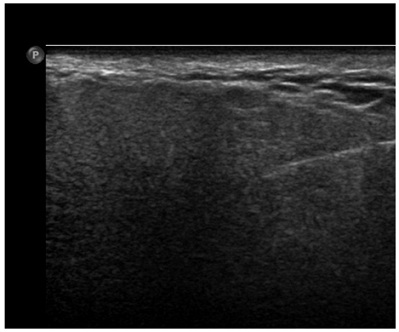

The Botox A injection was performed by an experienced interventional radiologist using ultrasound guidance. Patient was placed in supine position. The skin over the parotid and submandibular glands was disinfected with antiseptic. An ultrasound with linear transducer (5-12MHz) was used to identify the glands in real-time and for precise needle visualization. A 22G needle was used to inject Type A botulinum toxin to the submandibular gland and superficial lobe of the parotid gland. Type A botulinum toxin (Dysport®) was diluted in normal saline to a final concentration of 10 MU/ml. The submandibular and parotid gland were injected with 20 MU each. A total of 80 MU was used. Except for mild discomfort, there were no serious complications encountered (Figure 3).

Figure 3: Ultrasound guided injection of right parotid glands, which showed accurate intraglandular needle position.